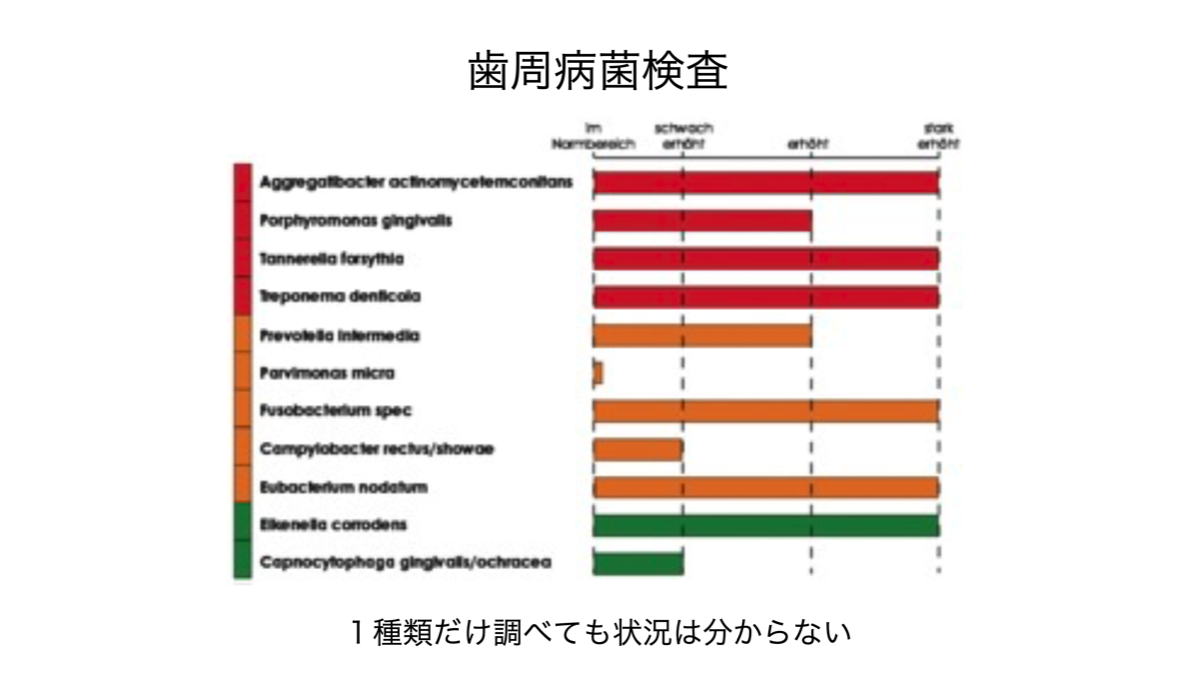

歯周病検査も色々ありますが、1つの提案として、現在住み着いている歯周病菌種を遺伝子検査で同定するだけではく、患者の炎症の起こりやすさも遺伝子検査で確認することは、リスクの評価として有用と考えます。精密に菌種を調べることで、歯周病の進行につれて菌の種類も大きく変化していくので、微生物学から見た歯周病のステージが判明します。また、炎症が起こりやすい体質であることが判れば、より一層抗炎症に取り組むことで、歯周病の進展が減速します。がんを始め、慢性炎症から継発する様々な疾患もあるので自らを知ることは予防医学的にも有用です。

歯周病検査も色々ありますが、1つの提案として、現在住み着いている歯周病菌種を遺伝子検査で同定するだけではく、患者の炎症の起こりやすさも遺伝子検査で確認することは、リスクの評価として有用と考えます。精密に菌種を調べることで、歯周病の進行につれて菌の種類も大きく変化していくので、微生物学から見た歯周病のステージが判明します。また、炎症が起こりやすい体質であることが判れば、より一層抗炎症に取り組むことで、歯周病の進展が減速します。がんを始め、慢性炎症から継発する様々な疾患もあるので自らを知ることは予防医学的にも有用です。